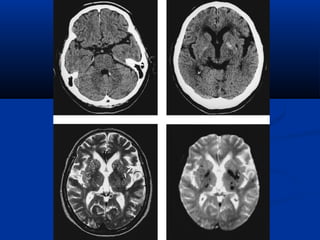

Diffusion Perfusion

Diffusion Tensor MRI

(DTMRI)

Choline vaø lactic acidPHOÅ COÄNG HÖÔÛNG

TÖØ

(SPECTROSCOPY/MRS)